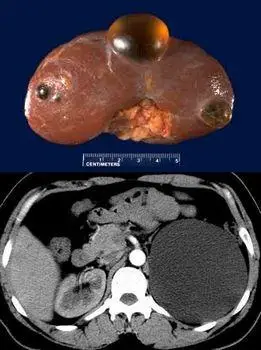

双肾多发囊肿

多发性肾囊肿

肾囊肿